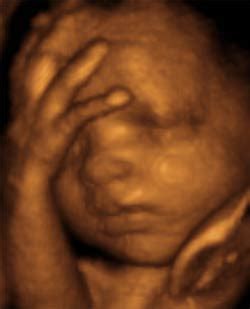

3D és 4D ultrahangvizsgálatok

A 3D és 4D ultrahangvizsgálatok modern ultrahangtechnikák, amelyek a hagyományos 2D (két dimenziós) ultrahangvizsgálatoknál részletesebb és térbeli képeket nyújtanak a magzatról.

3D ultrahangvizsgálat: A 3D ultrahangvizsgálat háromdimenziós képeket hoz létre a magzatról. Ezek a képek domborúak és részletesek, ami lehetővé teszi a vizsgálónak, hogy részletesebb betekintést kapjanak a magzat anatómiájába. A 3D ultrahang képek színekkel és árnyékokkal is gazdagítottak, ami még jobban megmutathatja a részleteket.

4D ultrahangvizsgálat: A 4D ultrahangvizsgálat ugyanazokat a háromdimenziós képeket nyújtja, mint a 3D, de további dimenziót ad hozzá: az időt. Ez azt jelenti, hogy a 4D ultrahang képek élőként jelenítik meg a magzat mozgását és viselkedését a méhben. A szülőknek így lehetőségük van arra, hogy lássák a magzatukat mozgás közben, például az arcot vagy az ujjakat mozgatva.

A vizsgálatok a várandósság bármelyik szakaszában elvégezhetők, azonban a kapott képek információtartalma, minősége és élvezhetősége eltérő lehet. A valósághű 4 dimenziós ultrahang felvétel készítésére a 26. hét körül van a legideálisabb időpont. Tapasztalataink szerint a leendő szülők leginkább két részletre kíváncsiak: a magzat nemére, és az arcára. A magzat nemének biztos meghatározása a várandósság 15. hetétől lehetséges, de már a 12-13. hét környékén is meg lehet próbálkozni vele.